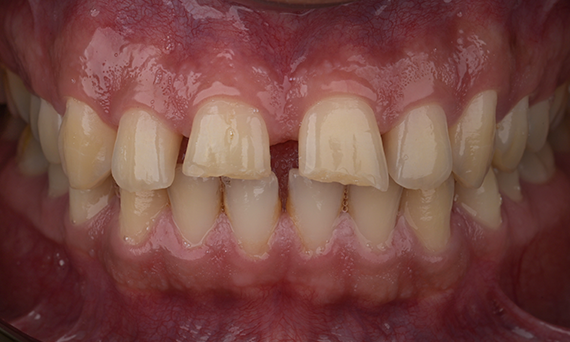

Aesthetic Rehabilitation of Amelogenisis Imperfecta

CEREC Tessera

An esthetic rehabilitation in the anterior region could be realized with labside CEREC Tessera restorations veneered with Celtra Ceram.

Before: The treatment objective was to rehabilitate the anterior maxilla and mandible for esthetic improvement. The clinical diagnosis revealed ameloenesis imperfecta.

After: Labside- fabricated restoration made from advanced lithium-disilicate ceramic CEREC Tessera and for the high esthetic result, the veneering with Celtra Ceram.